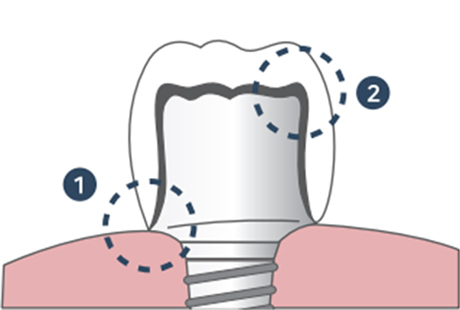

맞춤형 Abutment

맞춤형 Abutment1보철물과 잇몸 사이 들뜨는 공간이 없어 음식물 끼임이 적습니다.

(잇몸염증 예방)2보철물과 지대주 사이의 빈 공간이 적어 분산되지 않은 저작력에 의해 보철물이 깨질 위험이 적습니다.

심다치과 커스텀 어버트먼트

심다치과의 개인 맞춤형 지대주

저희 심다치과 지대주(어버트먼트)는 자연치아의 지대치 형태와

최대한 유사하게 제작되어 도재(보철물) 파절과 임플란트 주위염을 최소화 합니다.